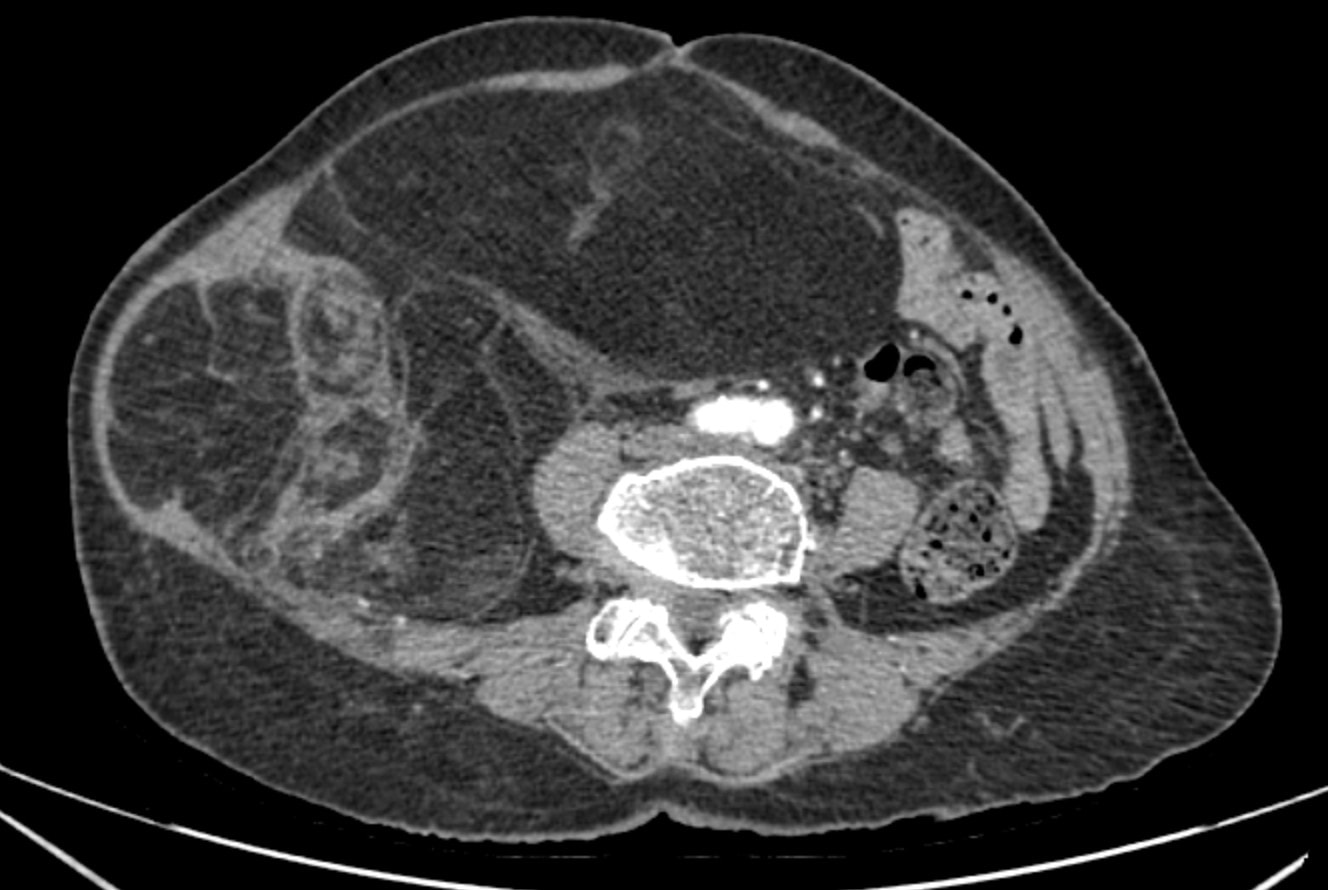

Chẩn đoán hình ảnh (CT ổ bụng có thuốc cản quang) cho thấy khối choán chỗ sau phúc mạc, kích thước 28 × 15 cm, cấu trúc hỗn hợp tổ chức mỡ – đặc , đè đẩy tạng trong ổ bụng nhưng không có dấu hiệu xâm lấn các tạng lân cận. Kết hợp lâm sàng và hình ảnh học, bệnh nhân được chẩn đoán sarcoma mỡ sau phúc mạc.